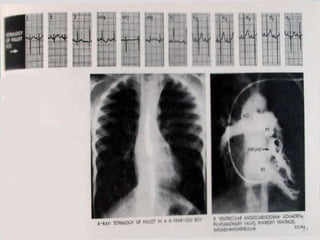

Radiografía de Tórax

• HVD

• Arco medio

excavado

• Flujo pulmonar

disminuido

• Aorta

prominente

17

Radiografía de Tórax • HVD • Arco medio excavado • Flujo pulmonar disminuido • Aorta prominente 17